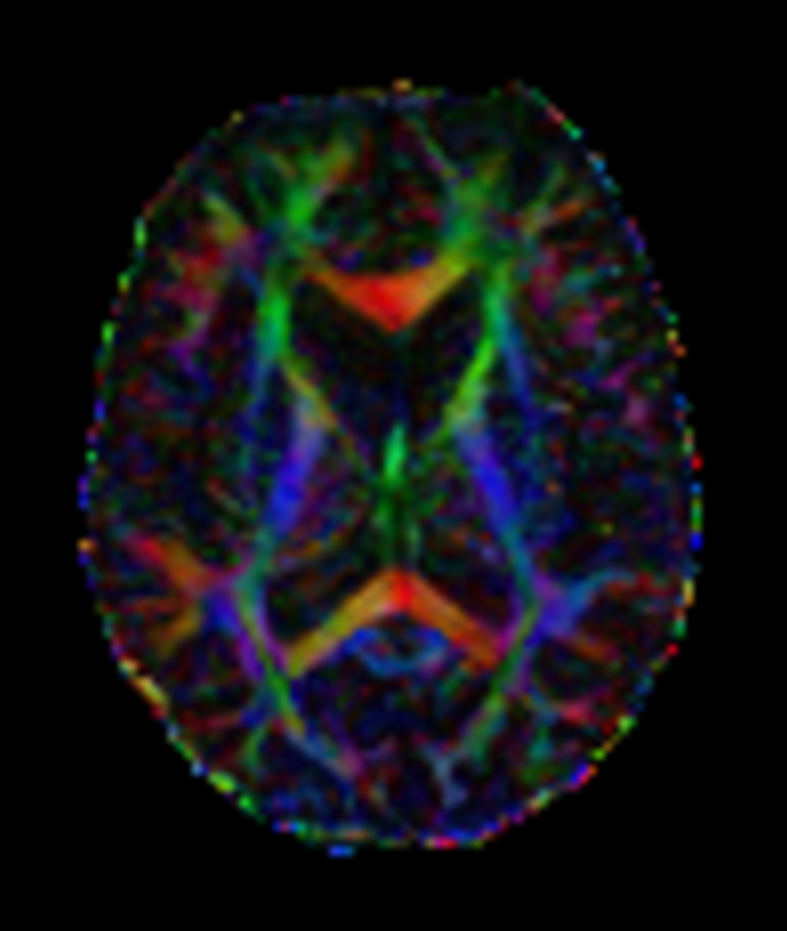

DTI b800 MultiBand SENSE 32 directions

-

DTI b800 MultiBand SENSE 32 directions (FA map)